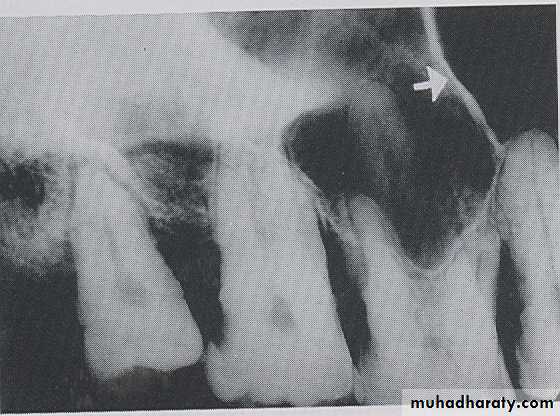

CORONOID PROCESS:

The coronoid process is a marked prominence of bone on the anterior ramus of mandible. Radiographically the coronoid process is not seen on mandibular periapical radiography but dose appears on maxillary periapical film as triangular radiopacity superimposed over the maxillary tuberosity region.